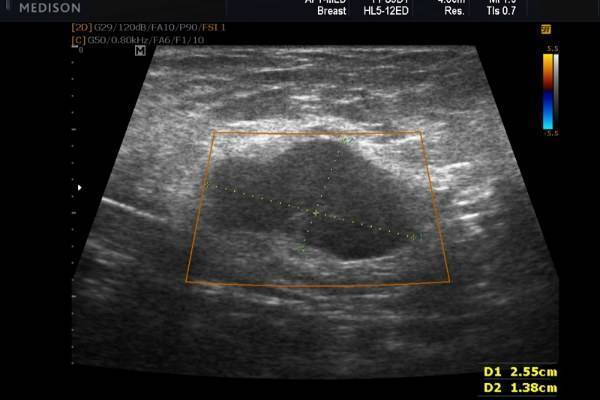

Лечение лактостаза врачом происходит под контролем ультразвукового датчика. Врач видит источник проблемы и знает, как ее решить максимально эффективно, безболезненно и без осложнений.

Врач делает осмотр, УЗИ молочных желез, ставит диагноз и назначает лечение. В зависимости от ситуации лечение может быть немедикаментозным, медикаментозным, физиотерапевтическим, а в серьезных, запущенных случаях врач может принять решение о необходимости хирургического вмешательства

Для проведения дифференциальной диагностики с маститом таким женщинам рекомендовано прохождение УЗИ грудных желез. Обычно врачи-сонологи описывают расширение протоков, наличие в них большого количества секрета, усиление кровотока.

Врач с помощью ультразвукового датчика производит диагностику лактостаза. Увидев источник проблемы и поняв способ ее решения, он выбирает наиболее эффективный и безболезненный вариант лечения. Более подробно схема выглядит так:

Основная цель ультразвукового исследования в маммологии – диагностика жидкостных и акустических плотных образований в груди, а также видимый контроль за лечебными и инвазивными манипуляциями. УЗИ диагностика является эффективным способом определить лактостаз. Сканограммы отражают застой в виде чрезмерно расширенных протоков молочной железы. Особенно четко можно увидеть расширение отдаленных протоков и синусов. При лактостазе, в отличие от мастита, наблюдается сохранение структуры молочной железы при отсутствии примесей крови и лимфы в тканях.

Существует компенсированный и декомпенсированный лактостаз (рекомендуем прочитать: как делать массаж при лактостазе?). Определить наличие одного из них можно с помощью фармако-сонографической пробы с применением питуитрина. Для начала женщину просят максимально сцедить грудь, а затем проводят УЗИ. После определения диаметра млечных протоков в организм вводится 1 мл питуитрина (внутримышечно). По прошествии 15-20 минут ультразвуковое обследование повторяют.